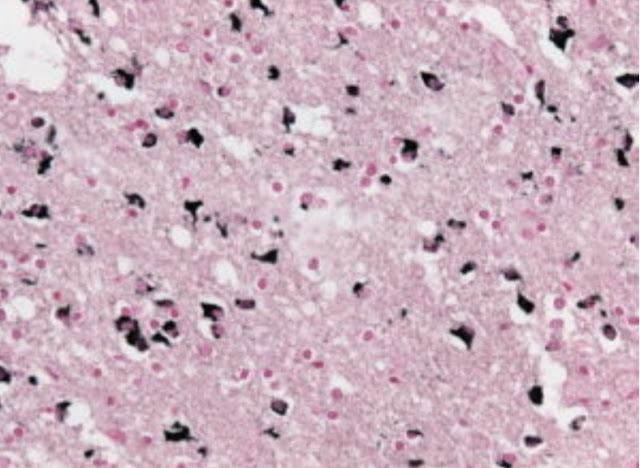

Prion is a proteinaceous infectious agent that causes fatal degenerative disease of nerves. Prions can be genetic, infectious or sporadic disease. The protein is able to structurally transform a normal occurring protein into an abnormal structural protein that is transmissible to other prion proteins. They are the main cause of transmissible spongiform encephalopathies.

When prions affect a healthy individual, they cause properly folded proteins to convert into amyloid form, in which proteins convert into aggregated beta pleated sheets, which accumulate which has potential to damage to the brain if accumulated in abnormal quantities.

The prion proteins are essentially present throughout the body in humans and in animals. However, the prion protein found in infections has a different structure and is resistant to proteases. Their entry to the brain happens through infection resulting in the progressive break down of neuron causing prion diseases. All prion proteins are not infectious.

This is a structurally altered form of the normal PrPc which is always infectious and causes disease. It is a discovered component for the infectious prion particles. The exact structure of the protein is still not known but it has structurally more than normal beta pleated sheets which form amyloid fibers, which eventually accumulate forming plaques.